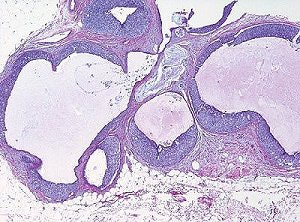

| Same patient as above. Histologic analysis of vacuum-assisted breast biopsy specimen shows ductal carcinoma in situ (DCIS) with solid architecture, intermediate nuclear grade, and central mucin (H and E, x40). Lee J, Kaplan JB, Murray MP, Mazur-Grbec M, Tadic T, Damir Stimac D, and Lieberman L, "Underestimation of DCIS at MRI-Guided Vacuum-Assisted Breast Biopsy" (AJR 2007; 189:468-474). |